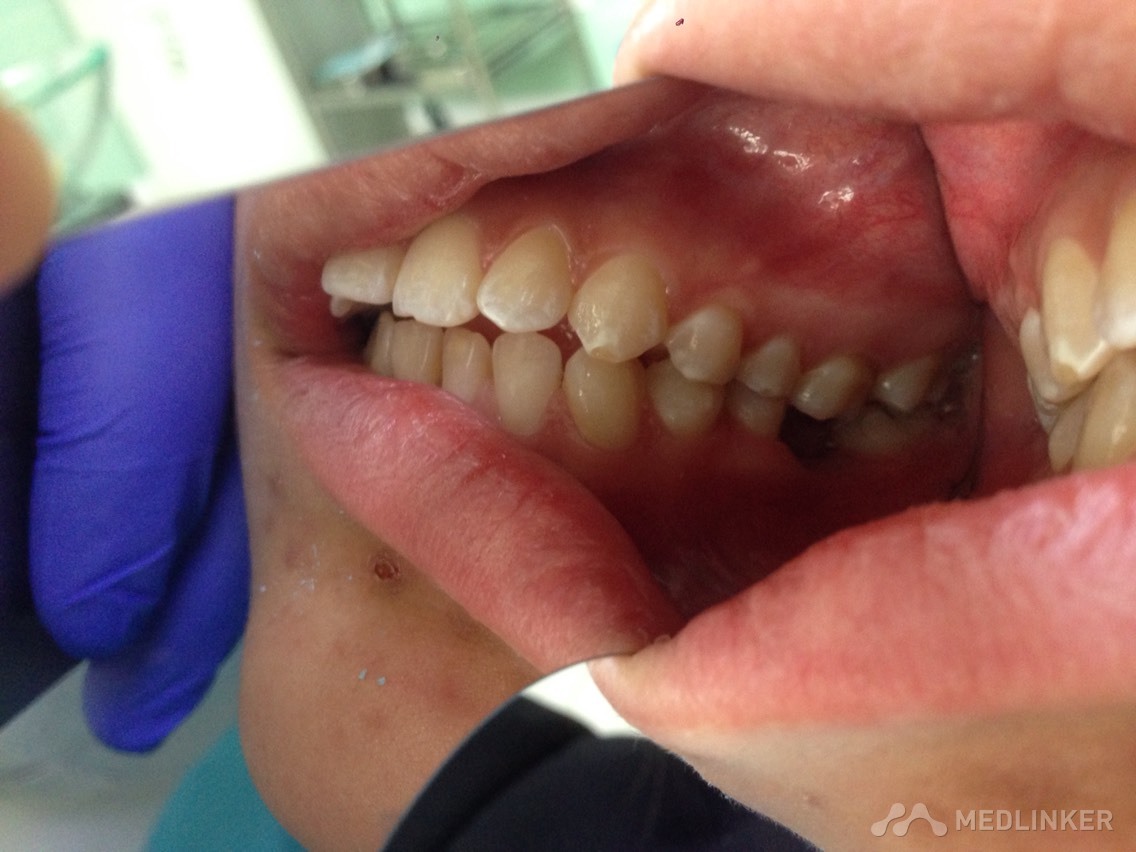

患者女,23岁,想做隐形无托槽矫正

上颌前牙牙列拥挤,下颌前牙散在间隙,下颌双侧第一磨牙缺失多年,开合